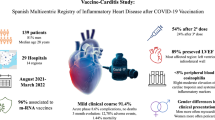

To evaluate clinical and cardiac magnetic resonance (CMR) short-term follow-up (FU) in patients with vaccine-associated myocarditis, pericarditis or myo-pericarditis (VAMP) following COVID-19 vaccination. We retrospectively analyzed 44 patients (2 women, mean age: 31.7 ± 15.1 years) with clinical and CMR manifestations of VAMP, recruited from 13 large tertiary national centers. Inclusion criteria were troponin raise, interval between the last vaccination dose and onset of symptoms < 25 days and symptoms-to-CMR < 20 days. 29/44 patients underwent a short-term FU-CMR with a median time of 3.3 months. Ventricular volumes and CMR findings of cardiac injury were collected in all exams. Mean interval between the last vaccination dose and the onset of symptoms was 6.2 ± 5.6 days. 30/44 patients received a vaccination with Comirnaty, 12/44 with Spikevax, 1/44 with Vaxzevria and 1/44 with Janssen (18 after the first dose of vaccine, 20 after the second and 6 after the “booster” dose). Chest pain was the most frequent symptom (41/44), followed by fever (29/44), myalgia (17/44), dyspnea (13/44) and palpitations (11/44). At baseline, left ventricular ejection fraction (LV-EF) was reduced in 7 patients; wall motion abnormalities have been detected in 10. Myocardial edema was found in 35 (79.5%) and LGE in 40 (90.9%) patients. Clinical FU revealed symptoms persistence in 8/44 patients. At FU-CMR, LV-EF was reduced only in 2 patients, myocardial edema was present in 8/29 patients and LGE in 26/29. VAMPs appear to have a mild clinical presentation, with self-limiting course and resolution of CMR signs of active inflammation at short-term follow-up in most of the cases.

A total of 44 patients were finally included in the study [females were 2 (4.5%)], with a mean age of 31.7 ± 15.1 years old. All the patients were aged ≥ 15 years old and 29 (65.9%) were < 35 years old. Patient selection flow-chart is reported on Fig. 1.

Mean time from the last vaccination dose to the onset of symptoms was 6.2 ± 5.6 days. The majority of the subjects included in the analysis received a vaccination with mRNA vaccine (Fig. 2) and predominantly after the second dose (Table 1).

Diagnosis at discharge of active myocarditis was reached in 28 (63.6%) patients (Fig. 3); myo-pericarditis in 13 (29.5%) and pericarditis in 3 (6.8%) (Fig. 4).